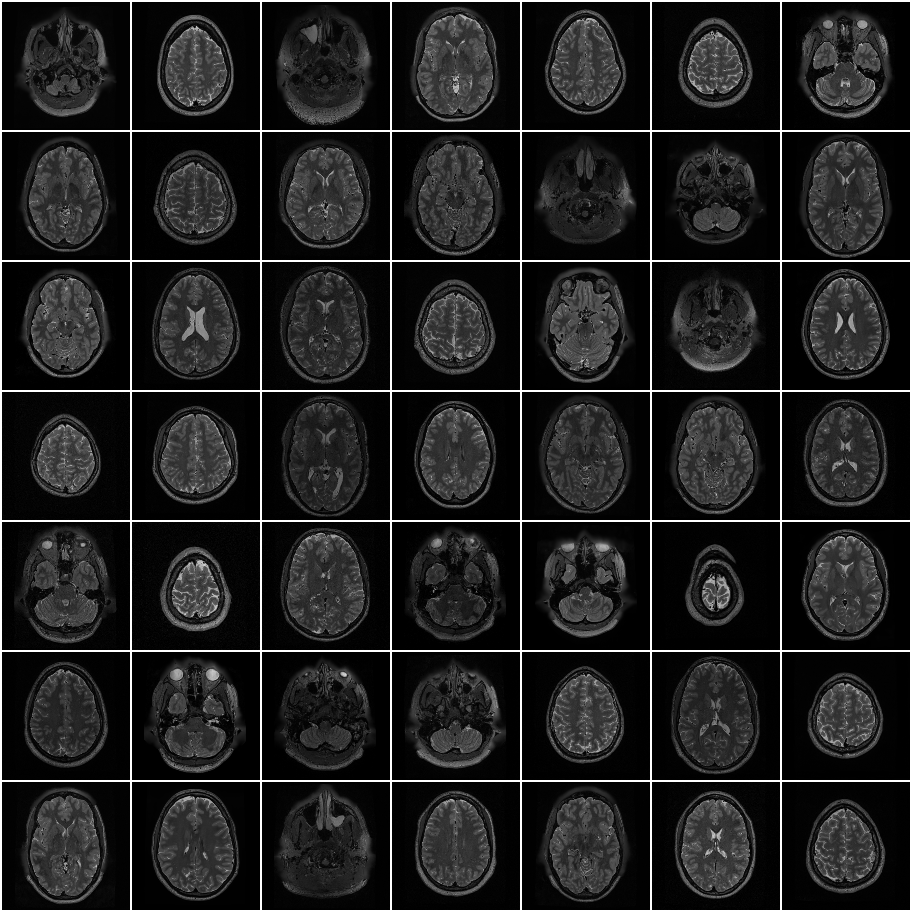

HCP T2w dataset

We utilize images from the publicly available Human Connectome Project (HCP) [51] T2-weighted (T2w) images dataset for the task of compressed sensing, which contains brain images from 47 patients. The HCP dataset includes cross-sectional images of the brain taken at different levels and angles.

Compressed sensing

We train a flow-based model from scratch on 10,000 randomly sampled images, utilizing the ncsnpp architecture [9] with minor adaptations for grayscale images. We employ compression rates , meaning . The measurement operator is given by a subsampled Fourier matrix, whose sign patterns are randomly selected. We evaluate our reconstruction algorithm’s performance on 200 randomly sampled test images.

We present the quantitative and qualitative results of compressed sensing in Tab. 1 and Fig. 4, respectively. As shown in Tab. 1, our method consistently achieves the best performance across varying compression rates . In Fig. 4, our method produces reconstructions that are more faithful to the original images, with fewer artifacts, leading to higher accuracy and clearer details.